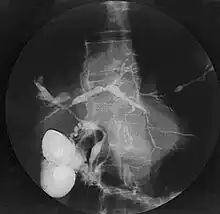

Cholangiogram of primary sclerosing cholangitis | |

Historically, a cholangiogram would be obtained via endoscopic retrograde cholangiopancreatography (ERCP), which typically reveals "beading" (alternating strictures and dilation) of the bile ducts inside and/or outside the liver. Currently, the preferred option for diagnostic cholangiography, given its noninvasive yet highly accurate nature, is magnetic resonance cholangiopancreatography (MRCP), a magnetic resonance imaging technique. MRCP has unique strengths, including high spatial resolution, and can even be used to visualize the biliary tract of small animal models of PSC.[21]